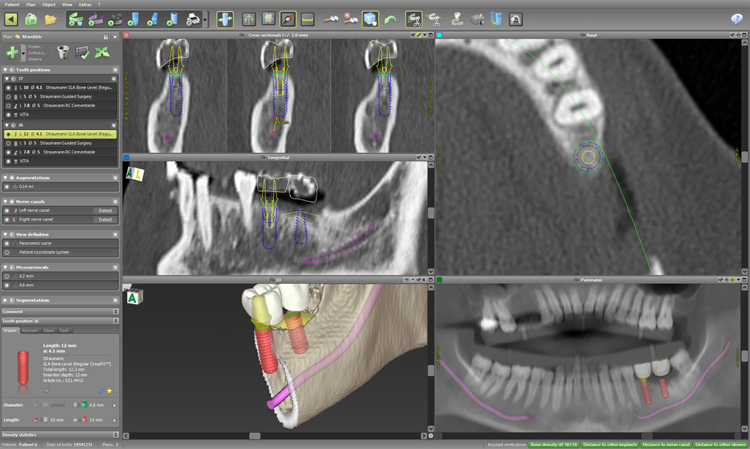

CTスキャン、痛みの少ないインプラント

インプラント治療を痛みなく安心して行うために、

信頼性の高いストローマンインプラント、専用の機材、日本国産の高性能歯科用CTスキャン、